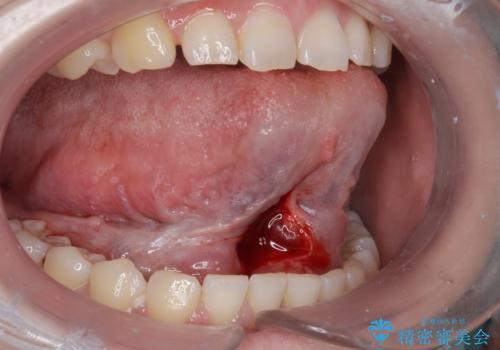

- 舌小帯を切りたいとの事で来院。

麻酔を行い、舌小帯切除術を行いました。

舌の可動域が広がりました。

- 外科手術のため、術後に出血、痛みや腫れ、違和感を伴います